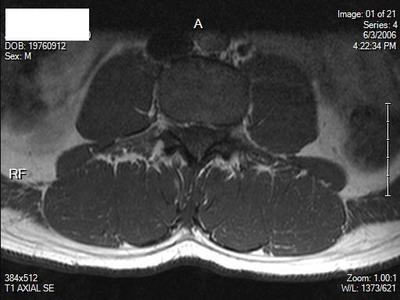

I'm 35 years old, male. Right hip pain, started as low back pain. Herniated disc L5S1, treated with ESI injections. Still have hip pain. Hurts when I flex my leg, SLR pain at about 45 degrees. My MRI and Xray are only of lumbar spine, however, do you see any abnormality of any bony or soft tissue of hip on these images? I understand it could be sciatica, which was the easiest thing they could come up with.

Two of the scan views are poor and I'm unable to determine what level; there's a suggestion of the fat squeezed out of the IVF on the right, but I wouldn't much store from that.

From what's visible of the hips they appear normal to me.

I'm trying to locate any other pathology. Is their any muscle atrophy? Or other bursitis, soft tissue, tendon?

There's normally fat in the IVF; if it's been squeezed out there's likelihood of a disc prolapse into the foramen.